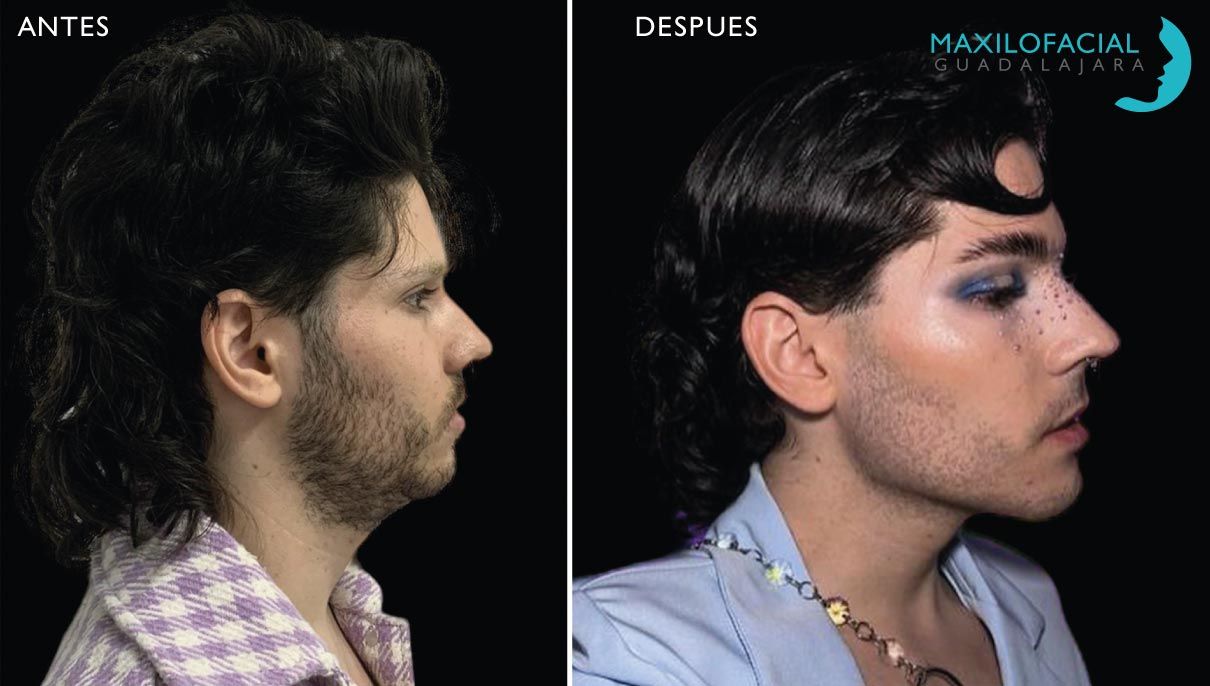

Feminización Facial

La cirugía de feminización facial (CFF) ha emergido como un campo revolucionario en el ámbito de la cirugía plástica, ofreciendo una transformación significativa para aquellos que buscan alinear sus características faciales con su identidad de género. Este procedimiento, diseñado específicamente para personas transgénero y no binarias, se ha convertido en un paso crucial en el viaje hacia la autenticidad y el bienestar emocional.

La CFF aborda diversas áreas del rostro, incluyendo la mandíbula, la nariz, la traquea y la frente, con el objetivo de suavizar las características masculinas y realzar las femeninas. La rinoplastia, por ejemplo, puede afinar la nariz, mientras que la reducción de la manzana de Adán puede contribuir a una apariencia más femenina. Estos procedimientos, cuando se realizan con expertos en cirugía de feminización facial, pueden lograr resultados notables.

Feminización Facial

La cirugía de feminización facial (CFF) ha emergido como un campo revolucionario en el ámbito de la cirugía plástica, ofreciendo una transformación significativa para aquellos que buscan alinear sus características faciales con su identidad de género. Este procedimiento, diseñado específicamente para personas transgénero y no binarias, se ha convertido en un paso crucial en el viaje hacia la autenticidad y el bienestar emocional.

La CFF aborda diversas áreas del rostro, incluyendo la mandíbula, la nariz, la traquea y la frente, con el objetivo de suavizar las características masculinas y realzar las femeninas. La rinoplastia, por ejemplo, puede afinar la nariz, mientras que la reducción de la manzana de Adán puede contribuir a una apariencia más femenina. Estos procedimientos, cuando se realizan con expertos en cirugía de feminización facial, pueden lograr resultados notables.